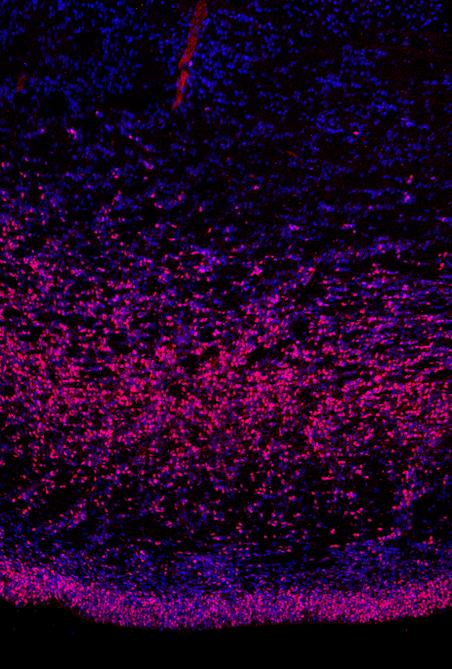

Dieses Bild ist im sich entwickelnden menschlichen Gehirn aufgenommen. Blau sind alle Zellkerne, rosa die neuralen Stammzellen dargestellt. Die untere Schicht Stammzellen haben alle Säugetiere. Die Schicht darüber zeigt die äußere Subventrikularzone mit neuen Stammzellen, die Wieland Huttners Labor 2010 entdeckt hat.